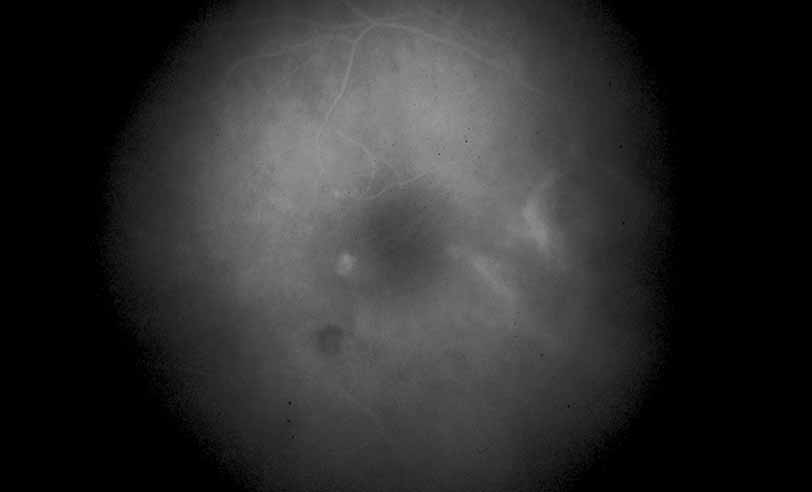

Fig. 3 Luetic neuroretinitis. Early-frame angiogram of eye of middle-aged man who presented with vision loss and a peculiar yellow---green discoloration of the outer retina and pigment epithelium. The patient was not known to be immunosuppressed, and subsequent serologic testing confirmed the presence of a positive VDRL and FTA-ABS. The early frame of the angiogram demonstrates a broad area of hypofluorescence corresponding to the clinical lesion. Note the subtle punctate leopard spots above the lesion.